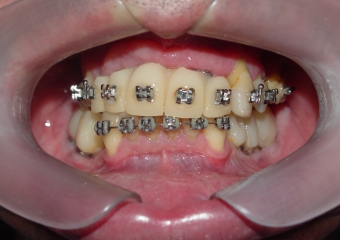

Provisórios Superior e Inferior em Março de 2013 - Clínica Cliniface

Provisórios Superior e Inferior em Março de 2013